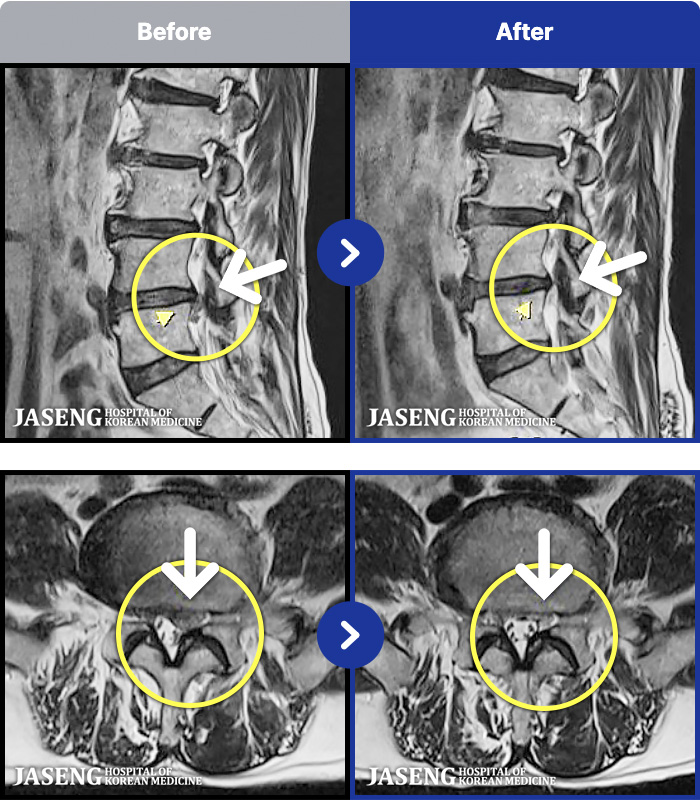

MRI ġ

1,237 MRI ũ ʸ Ȯϼ.